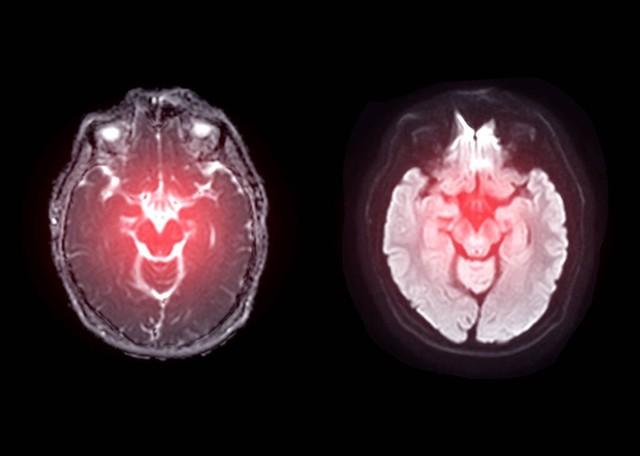

脑出血是一种突发性强、致死率高的疾病。据统计,我国每死亡5个人中,就有1人是因为脑出血去世的。更令人担忧的是,越来越多看似健康的人也突然遭遇脑出血的袭击。那么,究竟是什么原因导致了这种危险情况的发生?